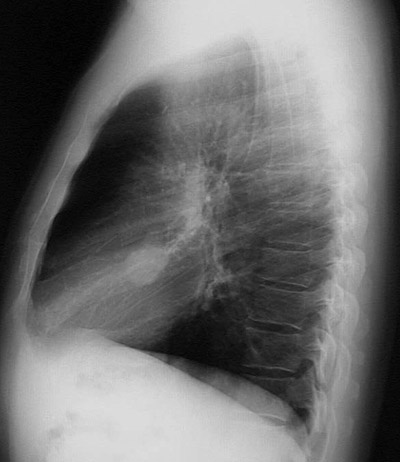

The lateral chest radiograph shown here demonstrates a discrete "coin lesion" that did not greatly increase in size over time and proved to be a pulmonary hamartoma.